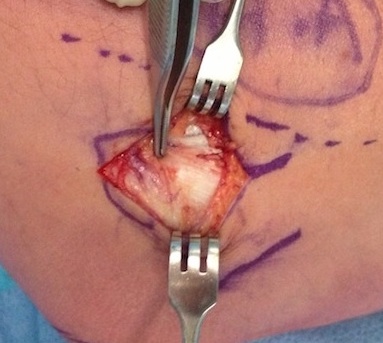

Open tennis elbow release

Technique

Incision centered on common extensor origin

- slightly anterior to radiocapitellar joint

- elevate ECRL (ECRL muscular at this point)

- ECRB is deep and posterior to ECRL

- detach ECRB from lateral epicondyle

- debride degenerative tissue and decorticate underlying common extensor origin

- +/- reattach ECRB with suture anchors

Post tennis elbow repair with anchor